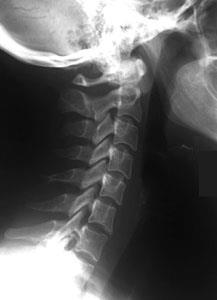

Aufnahmen von der Wirbelsäule zur Beurteilung von Veränderungen am Knochen, vor Operationen, zum Ausschluß von Knochenbrüchen und zur Verlaufskontrolle. Eine spezielle Vorbereitung der Patienten ist nicht notwendig. Moderne Röntgengeräte fertigen solche Aufnahmen mit einer geringen Strahlendosis an. Für alle, die sich genauer über die Auswirkung von Strahlen informieren wollen, empfiehlt sich ein Blick in Wikipedia.

Die Myelograhie dient der speziellen Darstellung des Wirbelkanals im Röntgen-Bild. Dazu wird zunächst durch Lumbalpunktion ein wasserlösliches Kontrastmittel in den Wirbelkanal eingebracht. Die Untersuchung wird bei besonderen Fragestellungen betreffs raumfordernder Prozesse des Spinalkanals, oder bei der Diagnostik ausgeprägter degenerativer Veränderungen im Bereich von Hals- oder Lendenwirbelsäule eingesetzt.